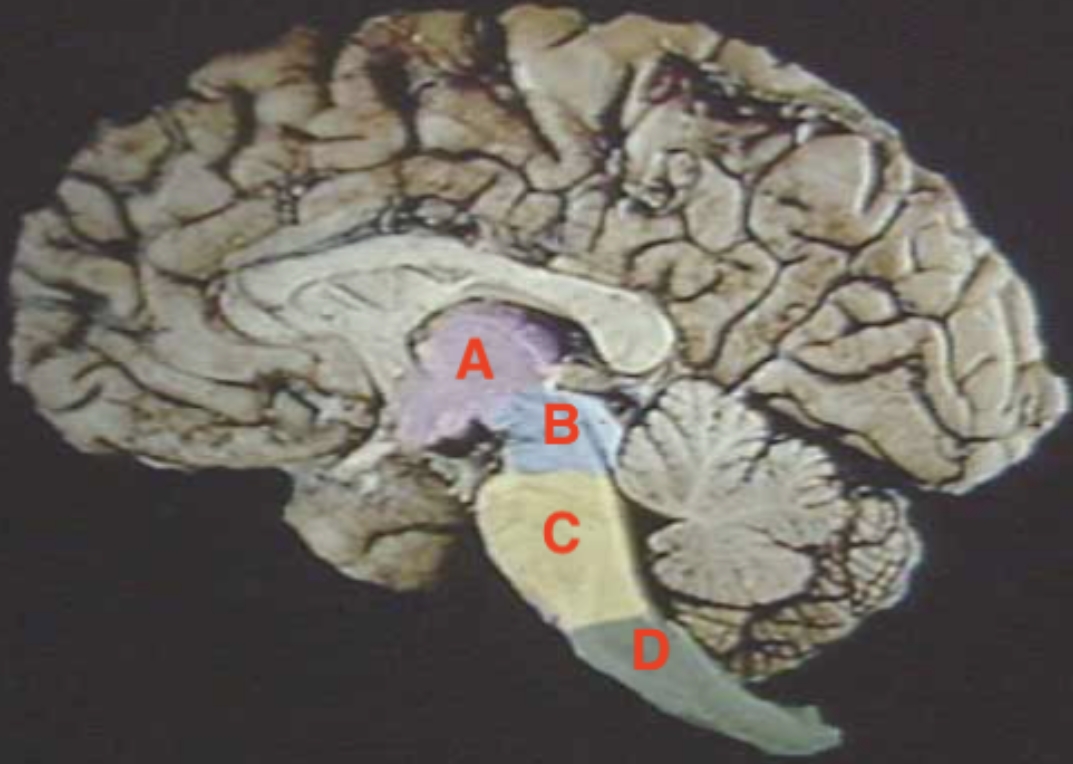

A

Hypothalamus + Thalamus

B

Midbrain

C

Pons

D

Medulla oblongata